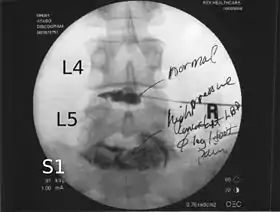

![]() Lumbar provocative discography showing a degenerated disc, L5-S1 with normal disc L4-L5 | |

Spinal MRI is the imaging of choice to investigate the spine and intervertebral discs.[1] Meanwhile, lumbar discography is used to demonstrate degeneration and herniation of lumbar intervertebral discs by injecting a dye into the nucleus pulposus of the discs. The procedure is also used to reproduce pain back pain for those who has such symptoms. Lumbar discography is also used to access the response of a subject to anaesthetic injection. Other uses includes: suspected discogenic pain without radicular sign (pain travelling to lower limbs along a dermatome), and confirmation of normal intervertebral discs above and below a site before spinal fusion.[1] However, evidence supporting the usefulness of lumbar discography in recognising intervertebral disc problems are limited.[1] There is no role for cervical or thoracic discography in diagnosing disc pathologies at the cervical or thoracic regions.[1][2]

Non-ionic contrast media such as iopamidol and iohexol are used.[1] Needles are inserted through the back into the disc near the suspect area, guided by fluoroscopic imaging. Fluid is then injected to pressurize the disc, and any pain responses are recorded.